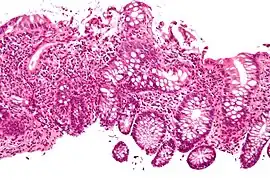

Cryptitis. H&E stain.

In histology, cryptitis refers to inflammation of an intestinal crypt.

Cryptitis is a non-specific histopathologic finding that is seen in several conditions, e.g. inflammatory bowel disease,[1] diverticular disease,[2] radiation colitis,[3] infectious colitis.